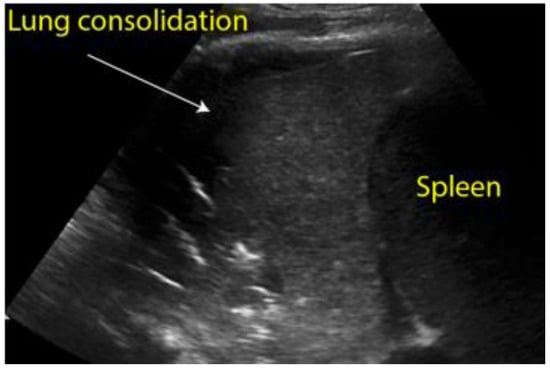

Figure 8. Longitudinal scan of left hypochondrium with presence of lung consolidation suggestive of pneumonia.

Ultrasound is also extremely useful in patients presenting with chest pain, cough, fever and dyspnea. These symptoms, associated with the presence of risk factors and an increase in inflammatory markers, can guide us towards the diagnosis of pneumonia, for which ultrasound has a high sensitivity, specificity and accuracy [42]. In particular, in very young or pregnant patients, ultrasound represents a valid option in diagnosing pneumonia [43].